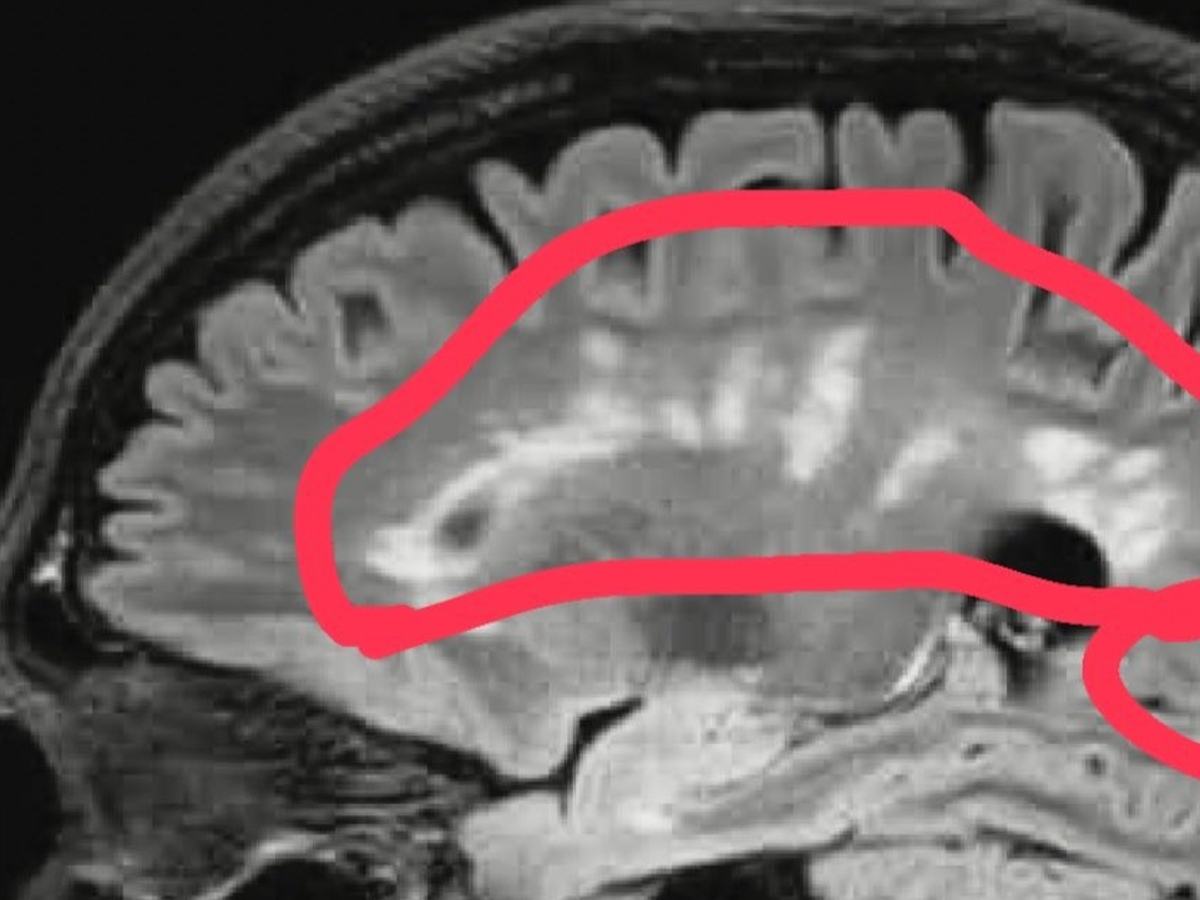

Hey Guys, I am sure you are aware i have been battling Multiple Sclerosis for about 13 years now.

Last week it took a very big decline and left me with stroke like effects, leaving half my face with facial palsy, and my memory cant remember certain words and how to make the sounds.